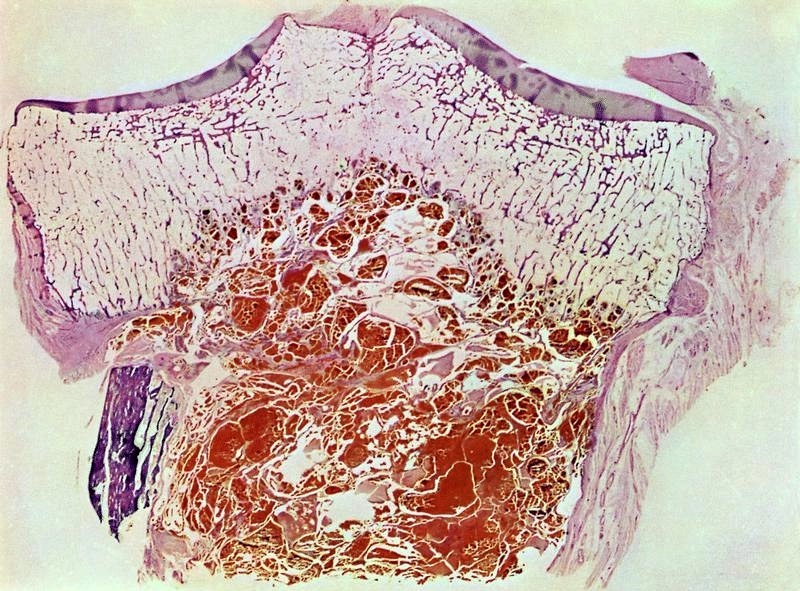

Gross description

- Conventional (high grade intramedullary) osteosarcoma:

- Intramedullary mass: usually a metaphyseal epicenter with cortical permeation and a soft tissue component that raises the periosteum

- Size (mean): 5 - 10 cm

- Cut surface: gritty and mineralized (hard); may have cartilaginous areas (chondroblastic osteosarcoma), hemorrhage, necrosis and cystic change

- Status postneoadjuvant chemotherapy:

- To gross: cut along long axis of tumor and map

- References: Cancer 1982;49:1679, Onco Targets Ther 2013;6:593

Gross images

A 12 year old girl has a 10.5 cm intramedullary mass in the distal femur, which was resected (see gross and microscopic images). High power views demonstrate bland spindle cells. Which of the following is most accurate regarding this tumor?

A. Most likely, genetic abnormality is amplification of the MDM2 gene. The tumor is a low grade central osteosarcoma.